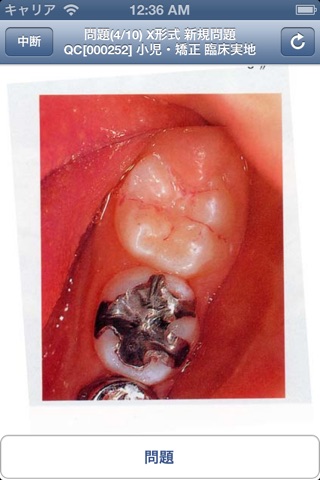

Pretest歯学は歯科医学系国家試験対策ソフトです。最近の難化傾向にある、国家試験に対して、場所を選ばず、国家試験形式の問題を学習できるようにデザインして作成しました。写真・図の表示をスマホ独特の「ピンチイン・アウト(拡大・縮小)」「スワイプ(移動)」に対応させ、狭いスマホの画面でも、なるべく読みやすいようにレイアウトされています。また、従来では、表示が難しかった歯科特有の歯式の表示も行うことができ、歯科学生にとって読みやすくなっております。また、ほとんどの問題には解説がついており、勉強する上での一助となれば幸いです。